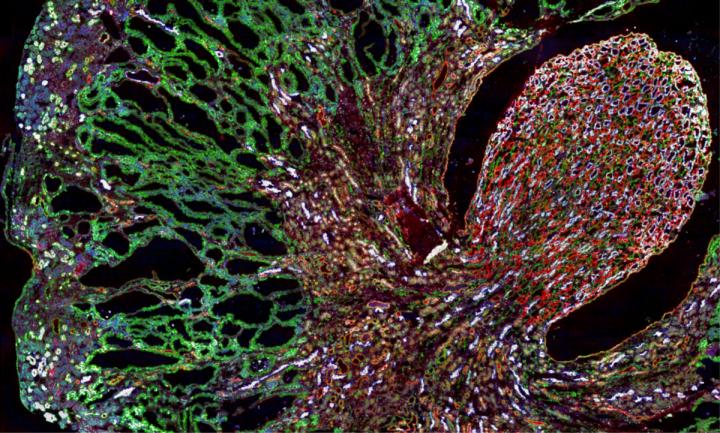

image: Misfolded MUC1-fs protein (green) builds up in the kidneys of a mouse model of MUC1 kidney disease.

Dvela-Levitt M, et al. Cell. 2019

The mutation results in the production of a truncated, misfolded protein dubbed MUC1-fs that collects in patients' kidney cells. As MUC1-fs accumulates, kidney cells die, eventually leading to kidney failure.

Experiments in human kidney cells, an MKD mouse model, and patient-derived kidney organoids showed that the cargo receptor traps MUC1-fs. This keeps the misfolded protein from reaching the lysosome (an organelle whose job is to chew up unwanted proteins), causing MUC1-fs to rise to dangerous levels in kidney cells.